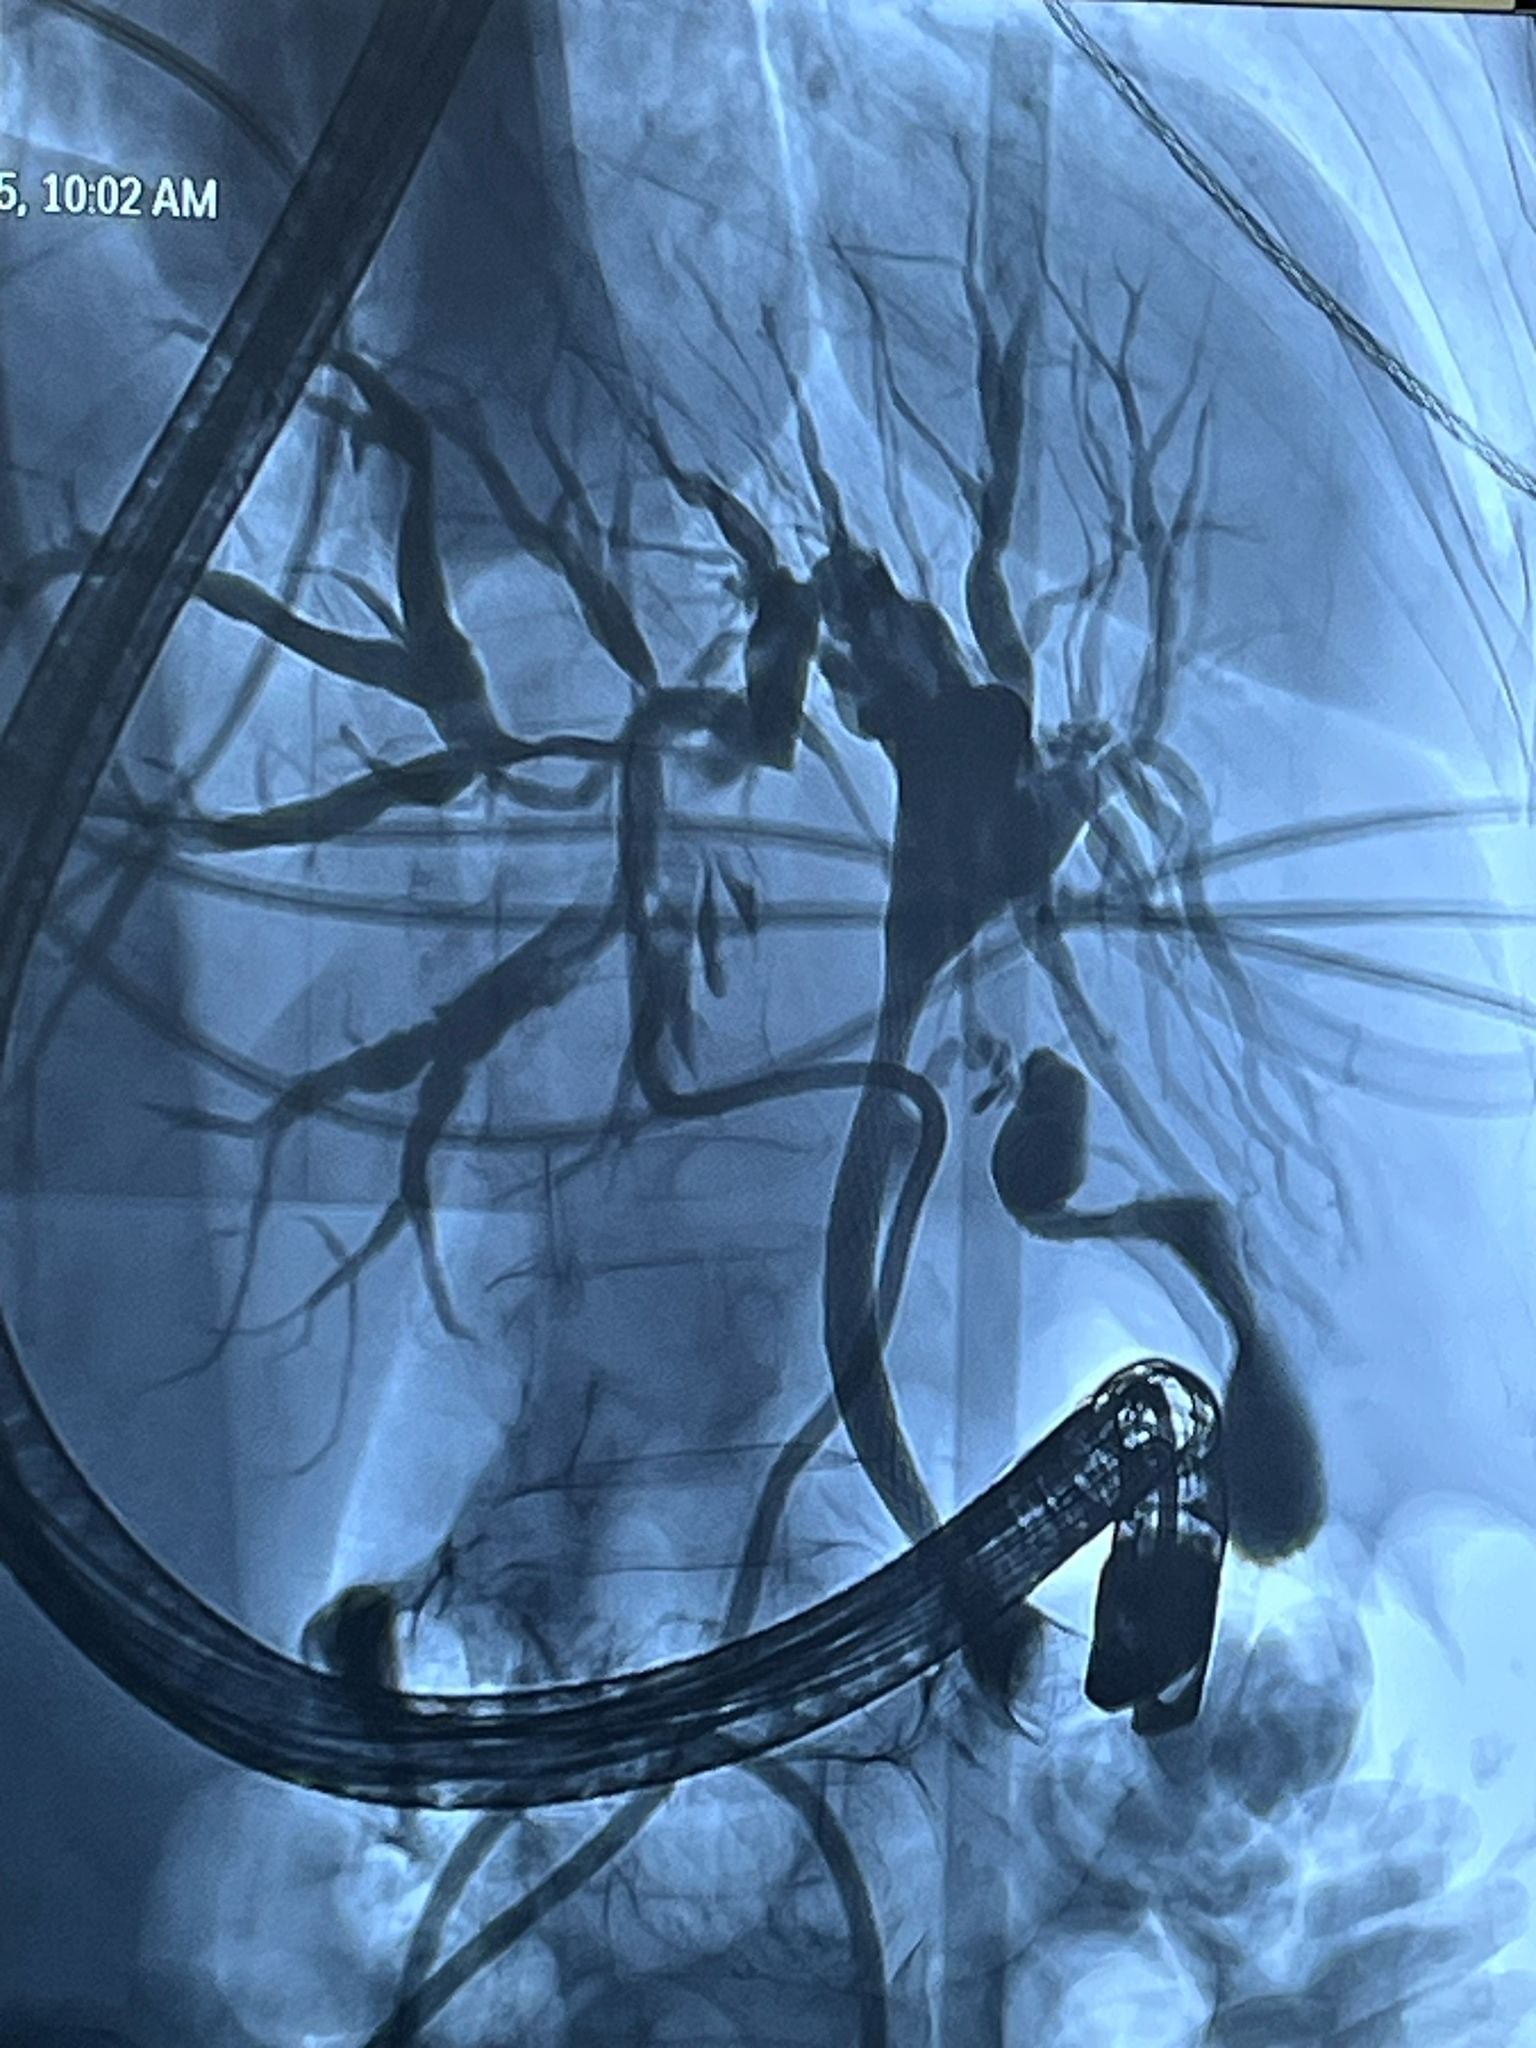

În prima etapă, echipa de Radiologie Intervențională a realizat cu succes un drenaj biliar percutan transhepatic. Ulterior, în a doua etapă, în colaborare cu echipa de Gastroenterologie, s-a efectuat montarea unui stent pe căile biliare extrahepatice, printr-o procedură hibridă, ghidată atât angiografic, cât și endoscopic.

„Colaborarea între specialiștii din Radiologie Intervențională, Gastroenterologie și ATI a făcut posibilă restabilirea drenajului biliar și evitarea complicațiilor majore, într-un caz cu un grad ridicat de dificultate. Această intervenție a fost posibilă datorită dotării spitalului cu angiograful utilizat în cadrul procedurii, achiziționat printr-un proiect coordonat de dr. Florin Grosu, cu sprijinul și efortul financiar al Consiliului Județean Sibiu,” mai transmit reprezentanții spitalului.